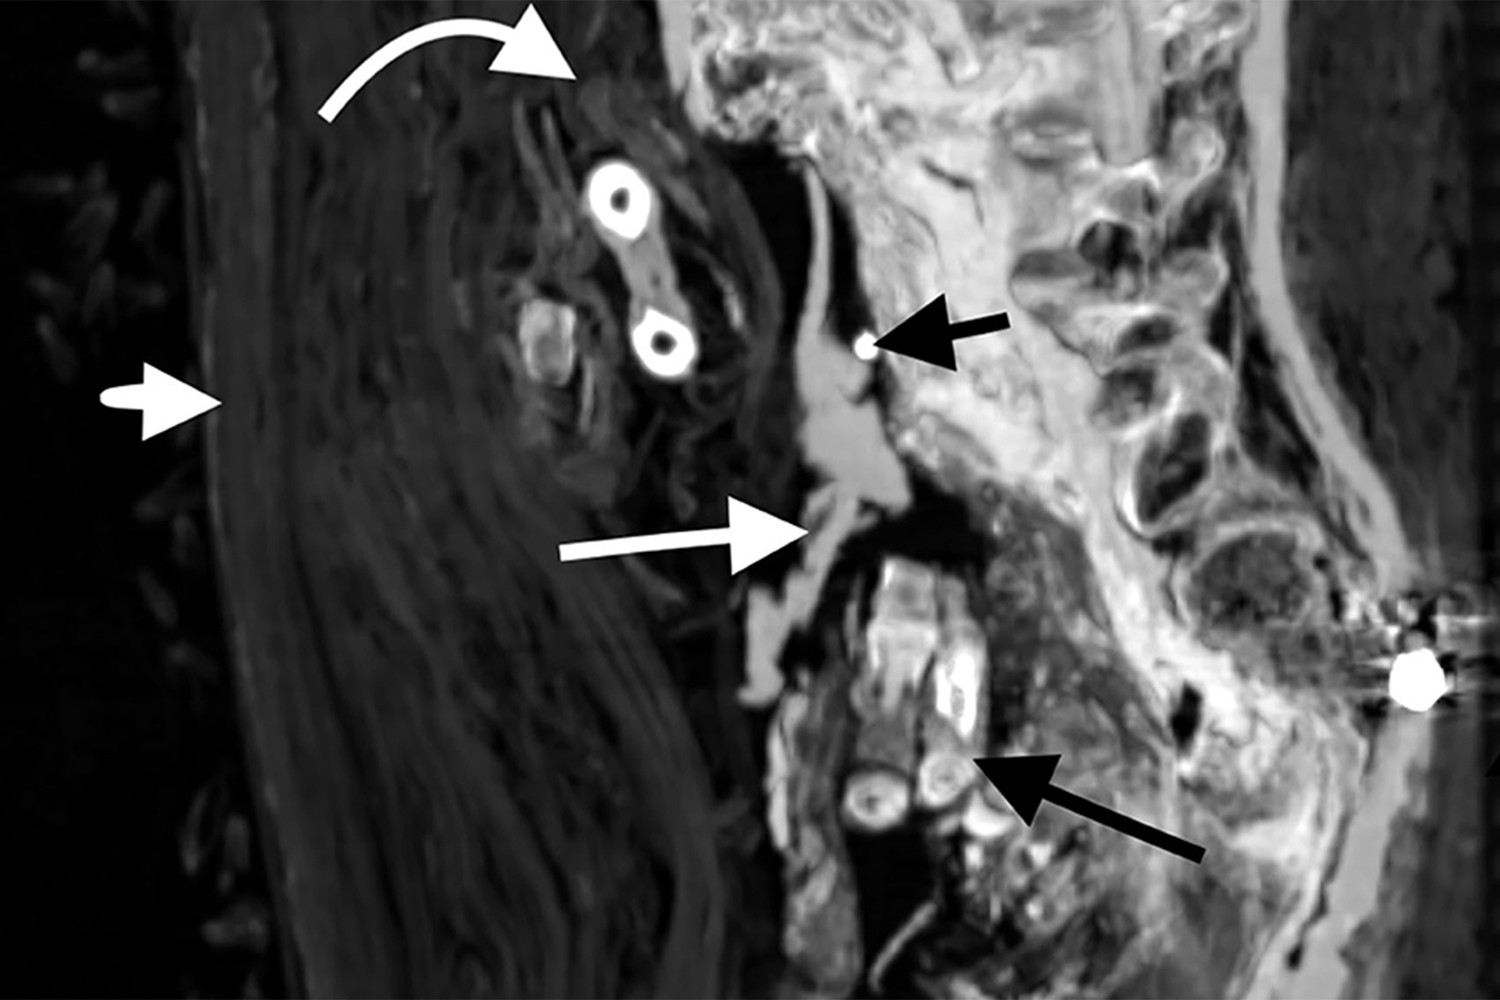

Мозг перед мумификацией не извлекался — он сохранился в черепе. Сам череп тоже был нетронут. Но внутренние органы были удалены через отверстие в боку, через него же тело было набито тканью. Сердце осталось на месте.

При повторном захоронении мумию явно пытались «отремонтировать» — пропитанные смолой бинты фиксировали оторвавшуюся из-за перелома шейных позвонков голову, прикрывали повреждения брюшной полости. Сломанным и вывихнутым конечностям придано подходящее положение. Ступни зафиксированы с помощью деревянных дощечек.